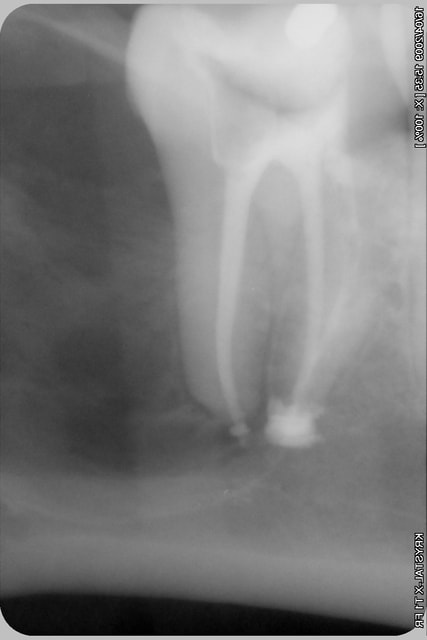

j'attends le resultat de l'irm

et ensuite ....

l'os est fin quand même, non?